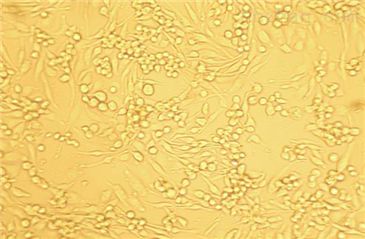

HTR8-SVneo

- 生长状态:

贴壁生长